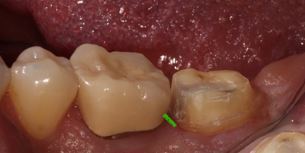

After adapting the matrix band so it seats further apically, it may still be challenging to have the band rest flush against the tooth. Gingival tissue may be present between the matrix band and the tooth’s subgingival margin in these instances. This increases the risk of material extending beyond the margin, leading to overhangs that are extremely difficult to correct.

To overcome this, the Belknap band can be utilized. Named after my friend and colleague, Dr. William Belknap, who taught me this technique, Teflon tape is placed between the band and the adjacent tooth.

This ensures an intimate adaptation between the band and the tooth, enabling the proper adaptation of restorative material during the margin elevation procedure. After the deep margin elevation technique is performed using the Belknap band, the Teflon tape and matrix band are removed, the new margin is refined, and the direct or indirect restoration can be completed.